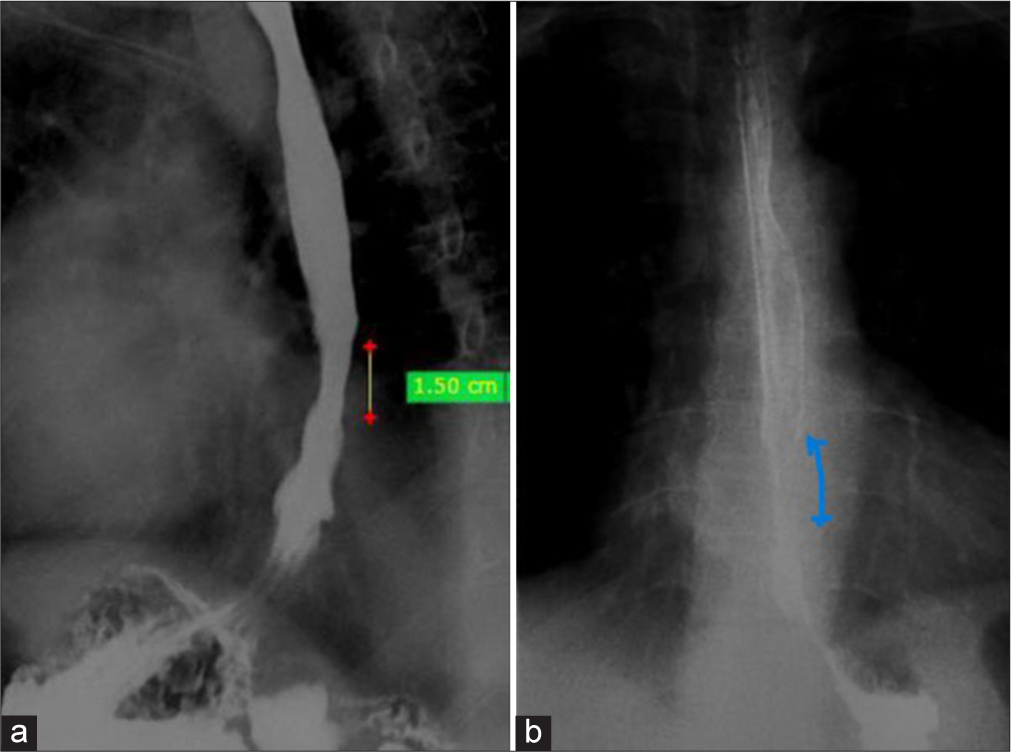

A 67-year-old male patient presented with benign peptic stricture. Computed tomography is done with formation of multiplanar views to see the site and extension of oesophageal stricture and to measure the wall thickness at the level of stricture. Figure 1a shows pre management computed tomography sagittal view showing concentric wall thickening for a segment of 4.2 cm denoted by yellow line. Figure 1b shows coronal view of computed tomography showing supra stenotic cone shaped dilatation proximal to stricture. Barium swallow was done which shows short segment luminal narrowing in lower thoracic oesophagus suggestive of stricture . Figure 2a shows Barium swallow lateral oblique view showing short segment luminal narrowing in lower thoracic oesophagus presented as yellow line and red dots. Figure 2b shows barium swallow antero-posterior view showing short segment luminal narrowing in lower thoracic oesophagus marked as blue line.

- (a) A 67-year-old male patient presenting with peptic stricture in the lower thoracic esophagus. Pre-management computed tomography sagittal oblique view showing concentric wall thickening for a segment of 4.2 cm denoted by yellow line. (b) Coronal oblique view showing suprastenotic cone-shaped dilatation showed by red arrow.

- (a) Red dots and yellow line shows Stricture (b) Blue line denotes short segment stricture.